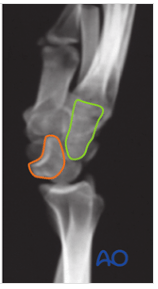

Salter-Harris classification for this fracture.

What is a Salter Harris IV fracture?